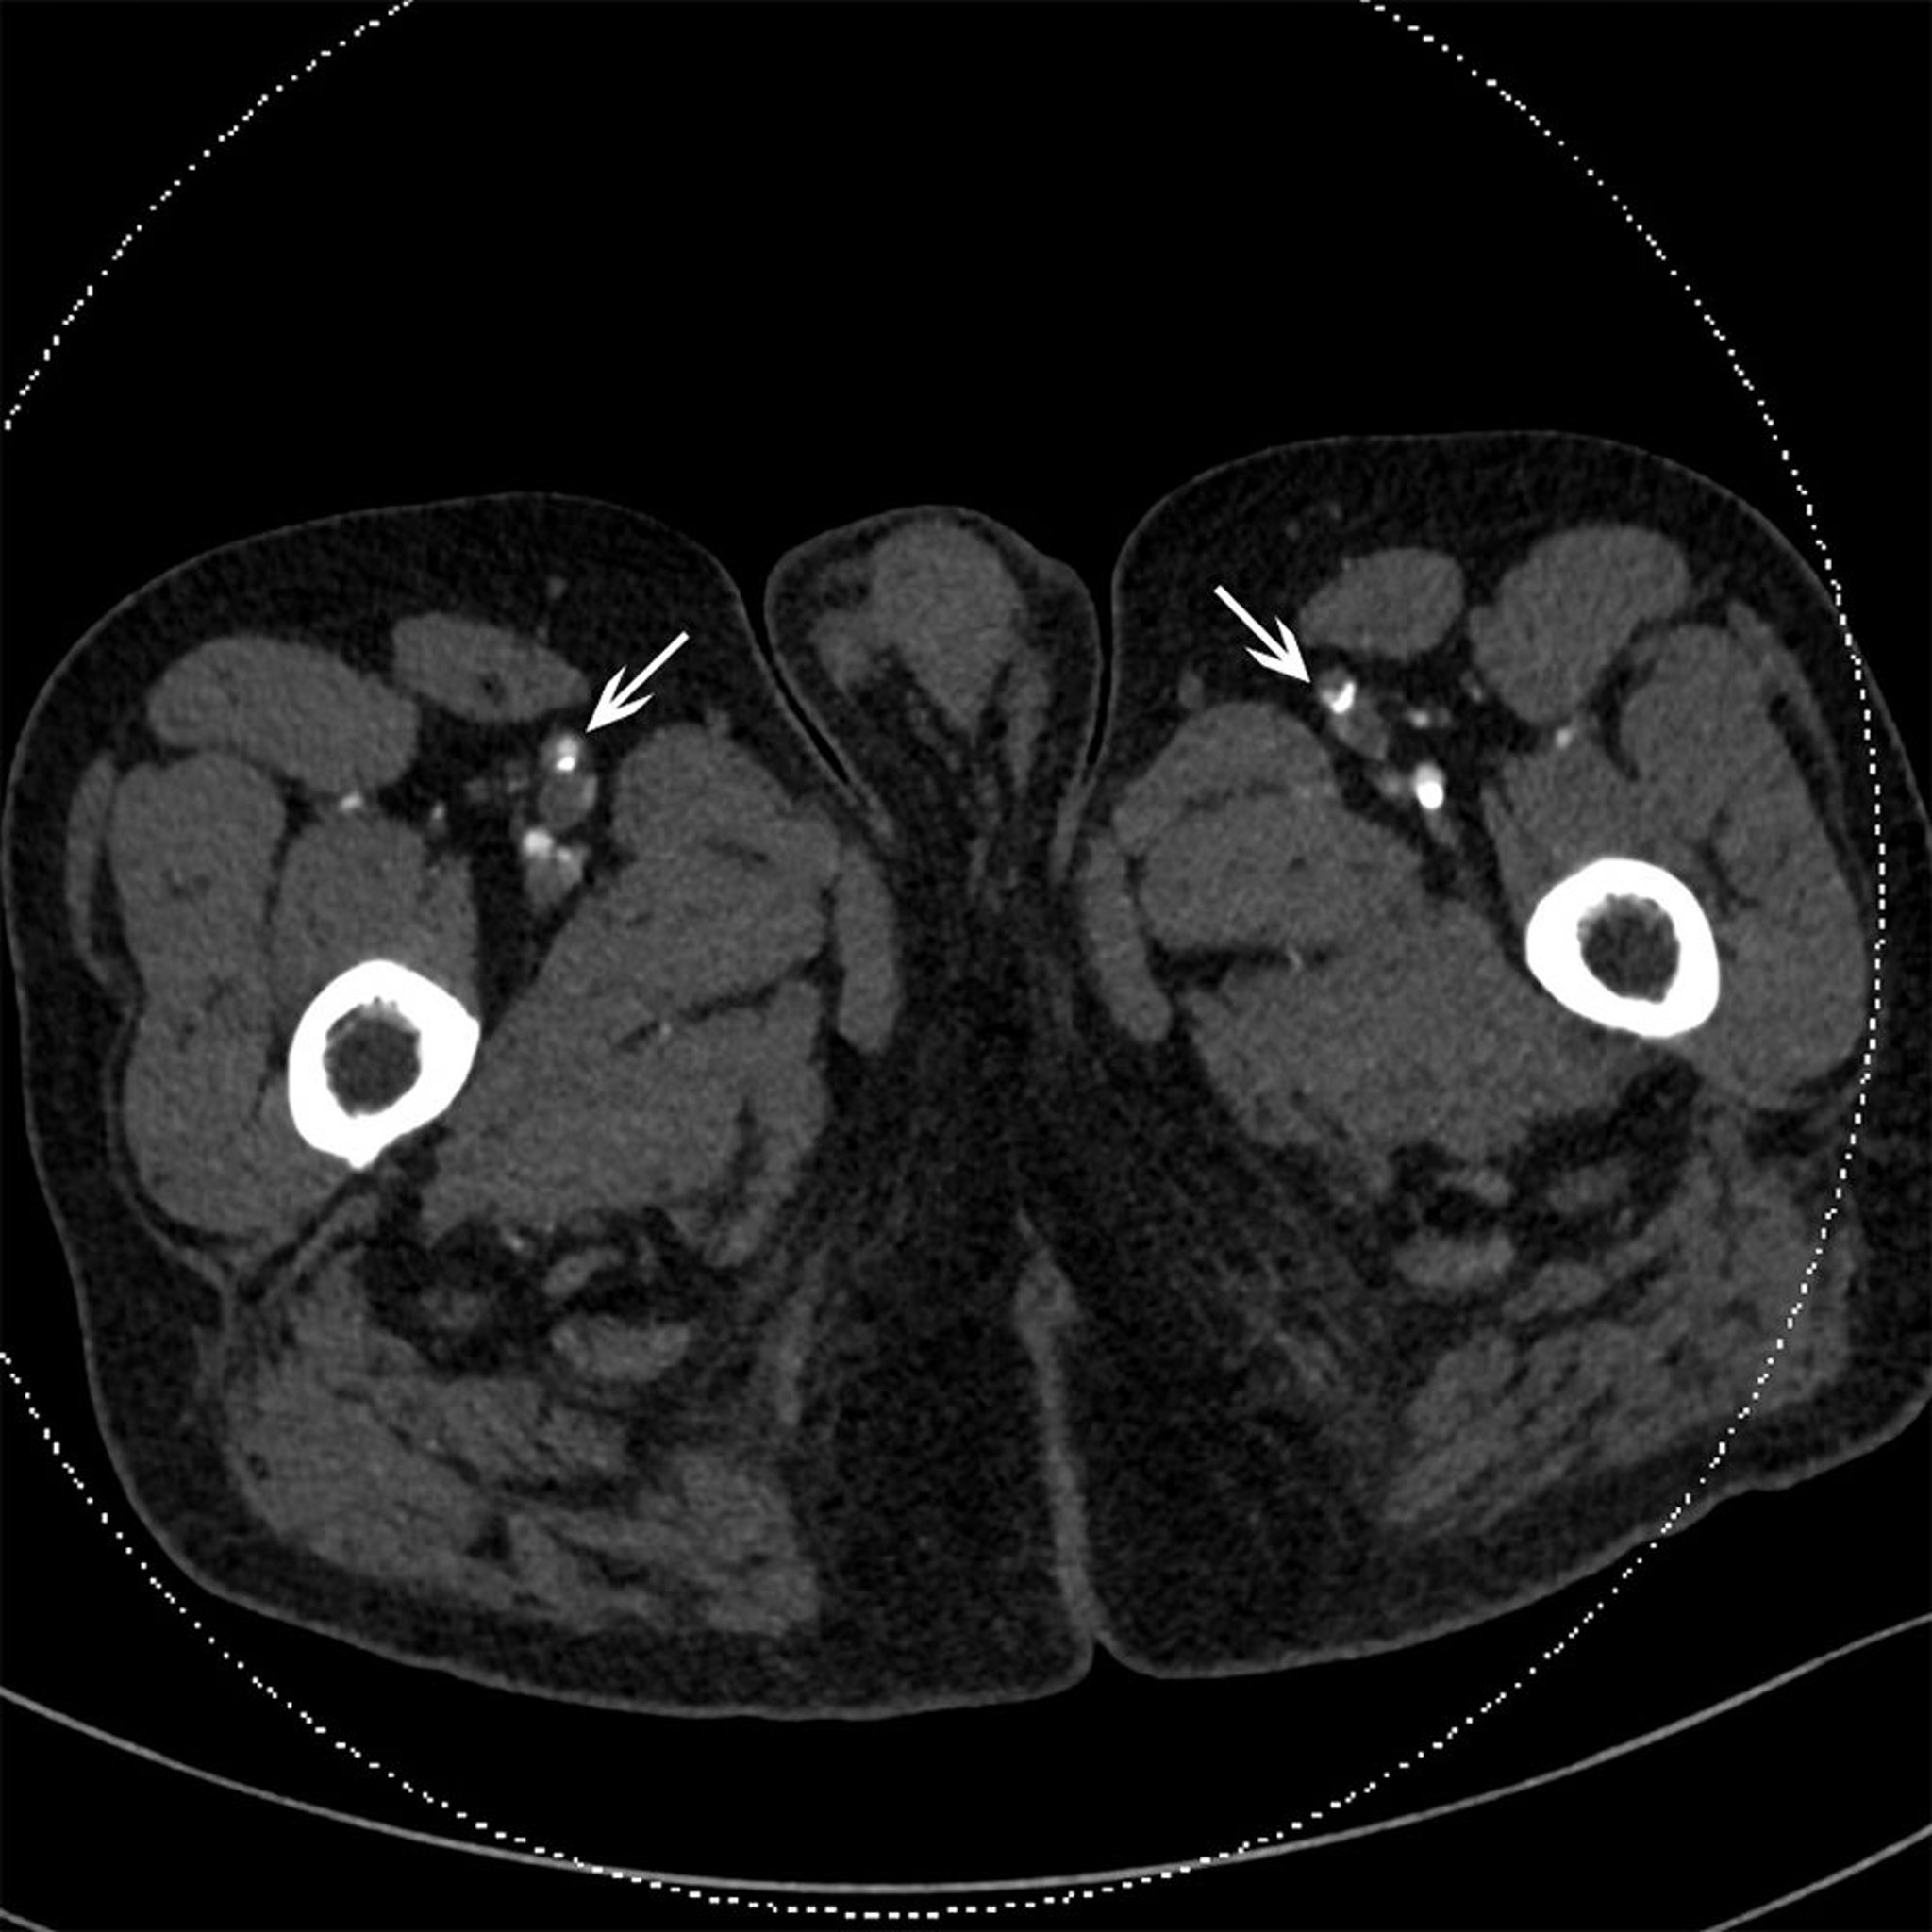

CT-Scan eines Patienten mit Okklusion der oberflächlichen Femoralarterien

Dieses CT zeigt beidseitig kalzifizierte Plaque in den oberflächlichen Femoralarterien (Pfeile).

© 2017 Elliot K. Fishman, MD.